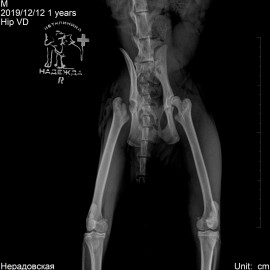

Через 2 месяца пришли с такими же симптомами относительно левой задней лапы (снимок 3). Была проведена операция (снимок 4).